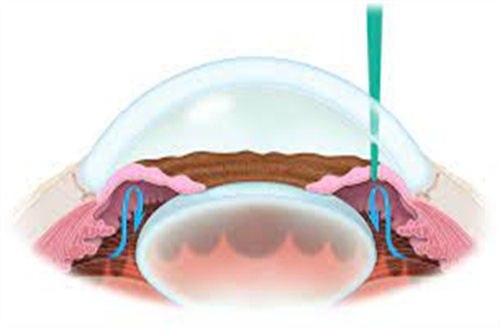

ICL晶体植入手术作为高度近视矫正的主流方案,凭借其可逆性、不损伤角膜的特点,成为越来越多近视患者的选择。

根据2025年爱尔眼科国内分院的收费标准,ICL晶体植入手术主要分为基础型ICL、散光矫正型TICL和飞秒辅助ICL三类,价格区间如下:

不损伤角膜:适合角膜薄、干眼症等激光手术禁忌人群。

可逆性强:晶体可随时取出,不影响未来其他治疗。

改善比较快:术后24小时即可正常用眼,3天稳定。

视觉质量高:尤其适合较高高度近视(>1000度)患者。